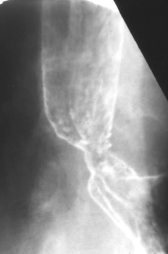

Hernie hiatale type I ( hernie hyatale de

glissement ) |

Image radiologique TOGD

une hernie hiatale de type glissement ( Type I ) ,

Le cardia glisse a travers hiatus diapragmatique

avec une partie de estomac |

Hernie

hiatale de Type I .Le cardia et une partie marquee

de estoma glissent a sus diapragmatique |